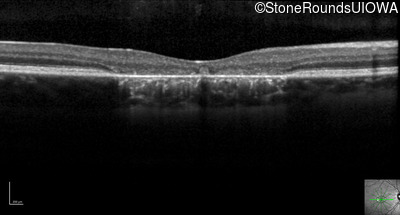

Optical Coherence Tomography - Right - 20/20 -2 sc

Exemplar / OCT Stack